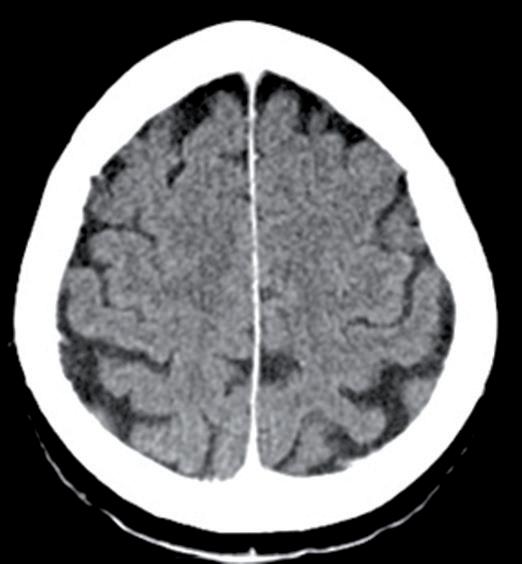

La paziente ha pertanto avviato una seconda linea di trattamento con T-DXd, ottenendo una progressiva riduzione delle lesioni meningee note ai successivi controlli mediante RM, fino ad arrivare a una situazione di stabilità che si mantiene tuttora a 24 mesi dall’avvio del trattamento (figura 1).

Figura 1. Immagini RM prima dell’avvio del trattamento e dopo 6 mesi.